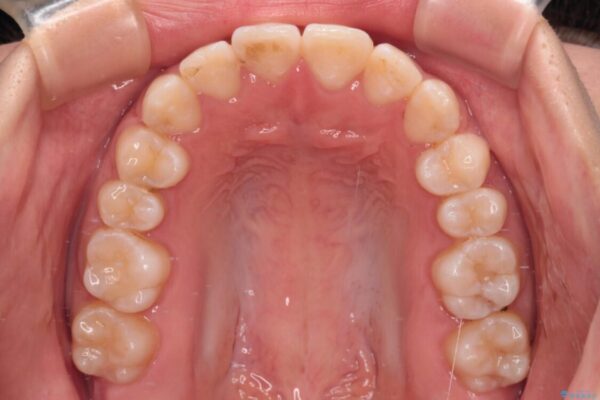

当初予定通り、1年で治療を終えることができました。

後戻り防止はマウスピースで行うため、急に自己管理が必要となるため、移動の最後をマウスピース矯正で行うことで、マウスピース非装着による後戻りリスクを回避する工夫をしています。

治療後

• 【モニター】短期間で終わりたい ワイヤー装置での非抜歯矯正 治療後画像